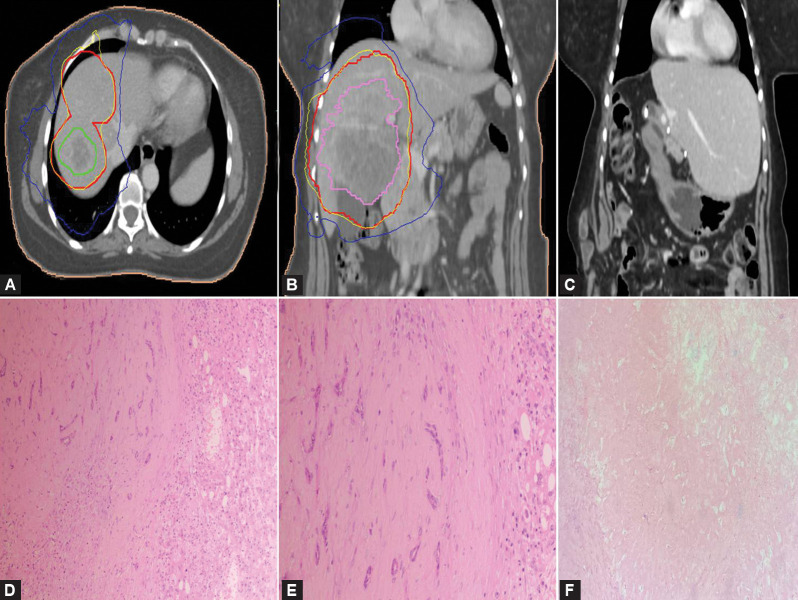

Materials and methods: For the present retrospective study, we identified 38 and 10 patients with resected perihilar and intrahepatic CCA. In perihilar CCA, adjuvant treatment was given as chemotherapy (n = 13) or chemoradiotherapy (n = 10). In intrahepatic CCA, neoadjuvant treatment was given with transarterial chemoembolization (TACE, n = 1) or chemotherapy plus stereotactic body radiation therapy (SBRT, n = 1), and adjuvant treatment was given to 7 patients with chemotherapy or chemoradiotherapy.

Results: In perihilar CCA, preoperative biliary drainage procedures were performed in 27 out of 30 patients with jaundice. The adjacent liver showed secondary sclerosing cholangitis (n = 5) and fibrosis (n = 19). Locoregional recurrence involved the hepaticojejunostomy anastomotic site and lymph nodes. In intrahepatic CCA, the adjacent liver revealed cirrhosis (n = 1), secondary sclerosing cholangitis (n = 1), and fibrosis (n = 6). The sites of recurrence were in the remnant liver and lymph nodes (n = 6). In perihilar CCA, the median overall survival (OS) and disease-free survival (DFS) rates were 30.1 months (95% CI: 22.9-37.4) and 15.1 months (95% CI: 9.74-20.5), respectively. The 2-year and 3-year OS were 60.5% and 44.7%, respectively. Multivariate analysis revealed a significant association of no adjuvant treatment with decreased DFS (p = 0.004), HR 4.03 (95% CI: 1.57-10.4). Recurrence showed an unfavorable association with OS (p = 0.056), HR 2.90 (95% CI: 0.98-8.66). In intrahepatic CCA, the median OS and DFS rates were 41.2 months (95% CI: 13.5-68.9) and 10.8 months (95% CI: 1.98-19.6), respectively. The 2-year and 3-year OS were 66.7% and 53.3%, respectively. The patient with multiple intrahepatic CCA lesions and treated with neoadjuvant chemotherapy and SBRT showed partial pathological necrosis after resection and was disease-free at 3.5 years.